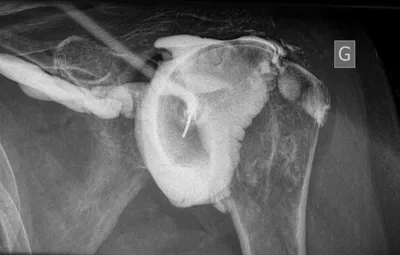

L'arthrographie est un examen radiologique qui consiste à introduire un produit de contraste dans une articulation, le plus souvent pour la réalisation d'un arthroscanner ou pour guider une infiltration et être sûr du bon positionnement de l'injection du produit prescrit.

La diffusion du produit de contraste pendant l'injection permet de faire des diagnostics :

- de capsulite rétractile

- de lésion tendineuse et notamment de la coiffe

- de déceler des ulcérations des cartilages